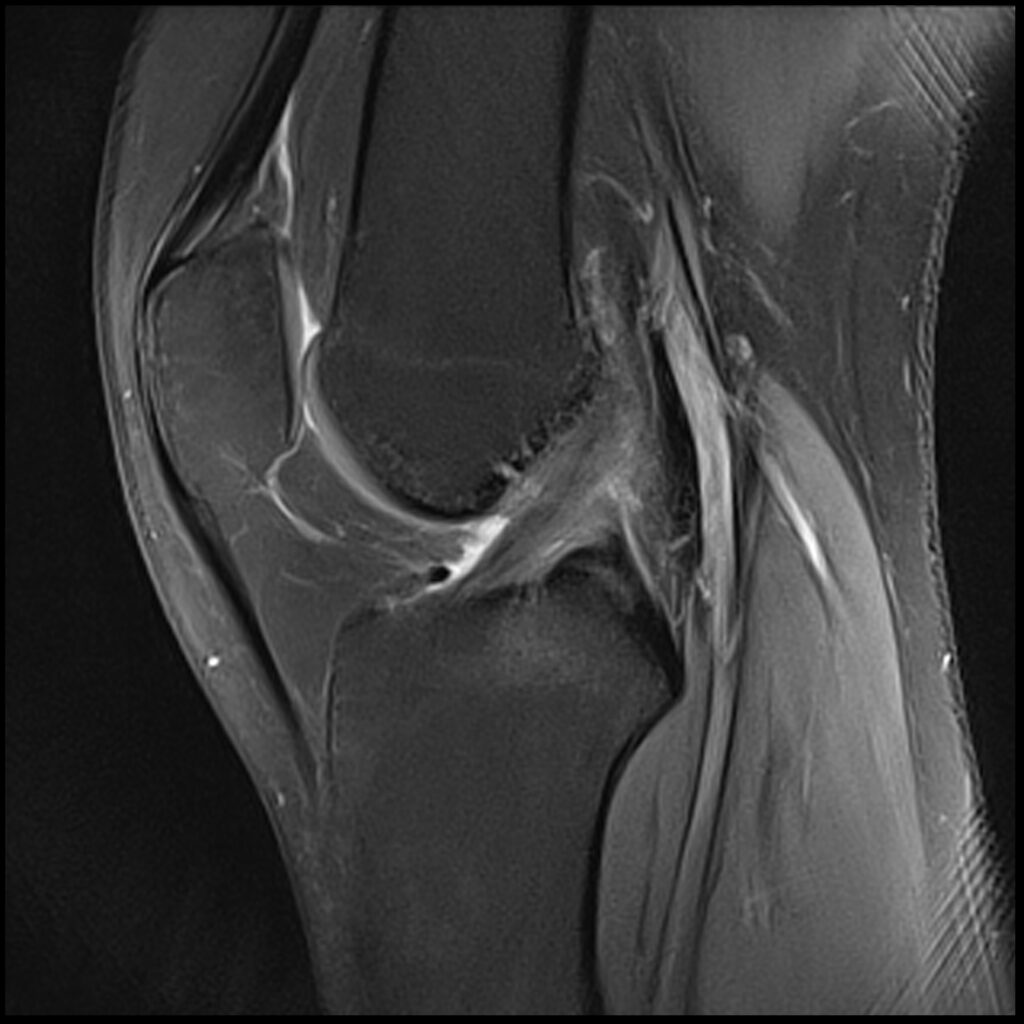

Patient D, age 19, sustained a competitive tumbling injury that involved a hard landing with the pathognomonic plant and pivot that directly tractions the ACL along its doubly obliqued path. The first MR scan was done the day after the trauma. She was initially treated 5 days post-injury. Her knee effusion was completely aspirated, then replaced with 3cc of autologous platelet-rich plasma and 5cc of platelet-poor plasma. Using ultrasound guidance, the ACL origin at the posterior femur was treated after carefully avoiding the vasculature and nerves. She was then instructed not to bear weight for 3 days, then use crutches/assisted weight bearing for 2 weeks. She was then to use a compression knee sleeve during sports or exercise. At her follow-up visit at 4 weeks, she was still having some instability at times and lateral knee pain. Her knee was evaluated with an ultrasound, and any areas of pathology seen were treated with hypertonic dextrose injection and needling technique. This included her medial and lateral collateral ligaments, and the patellar tendon and ligament. At 12-week follow-up, she continued to have some minor issues with her knee, so another evaluation and treatment were performed with hypertonic dextrose to the injured ligament and tendon areas found on the ultrasound examination. We obtained a new MR for her 16-week follow-up and noticed the ACL had re-ligamentized, and she reported full function and return to exercise. At 5-year follow-up, she claimed she was fully active, pain-free, but no longer tumbling.

Patient D After